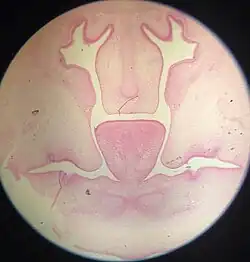

![]() Frontal section of nasal cavities of a human embryo 28 mm. long (Kollmann) at about forty-four days. The two palatine processes can be seen here post-elevation in a horizontal position. The medial edges of the palatine processes are yet to fuse and form the roof of the oral cavity. | |